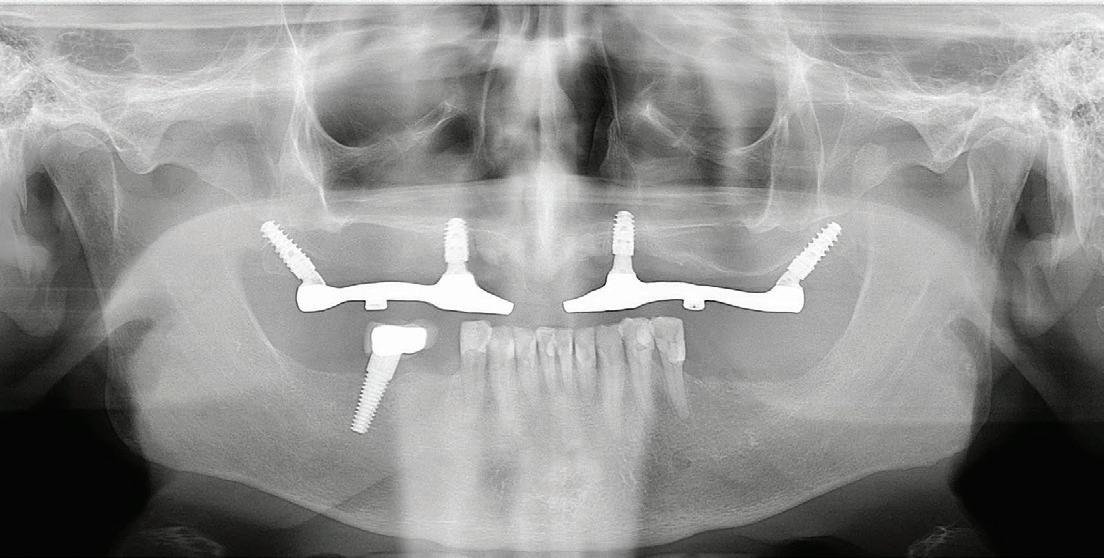

55 A Follow-up to the July/August Pterygoid Implant Article

Dr. Lance Karp Sarasota